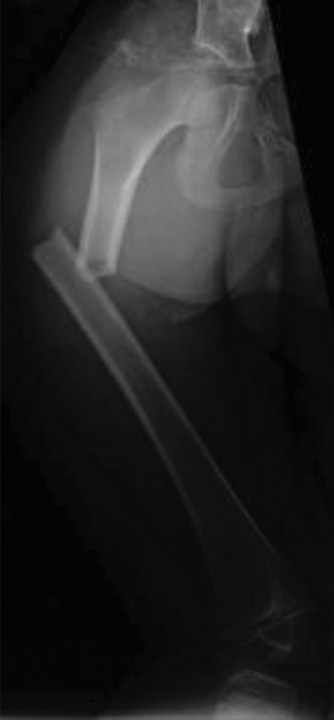

CASE 47 The patient is a 74-year-old man involved in a motor vehicle collision …